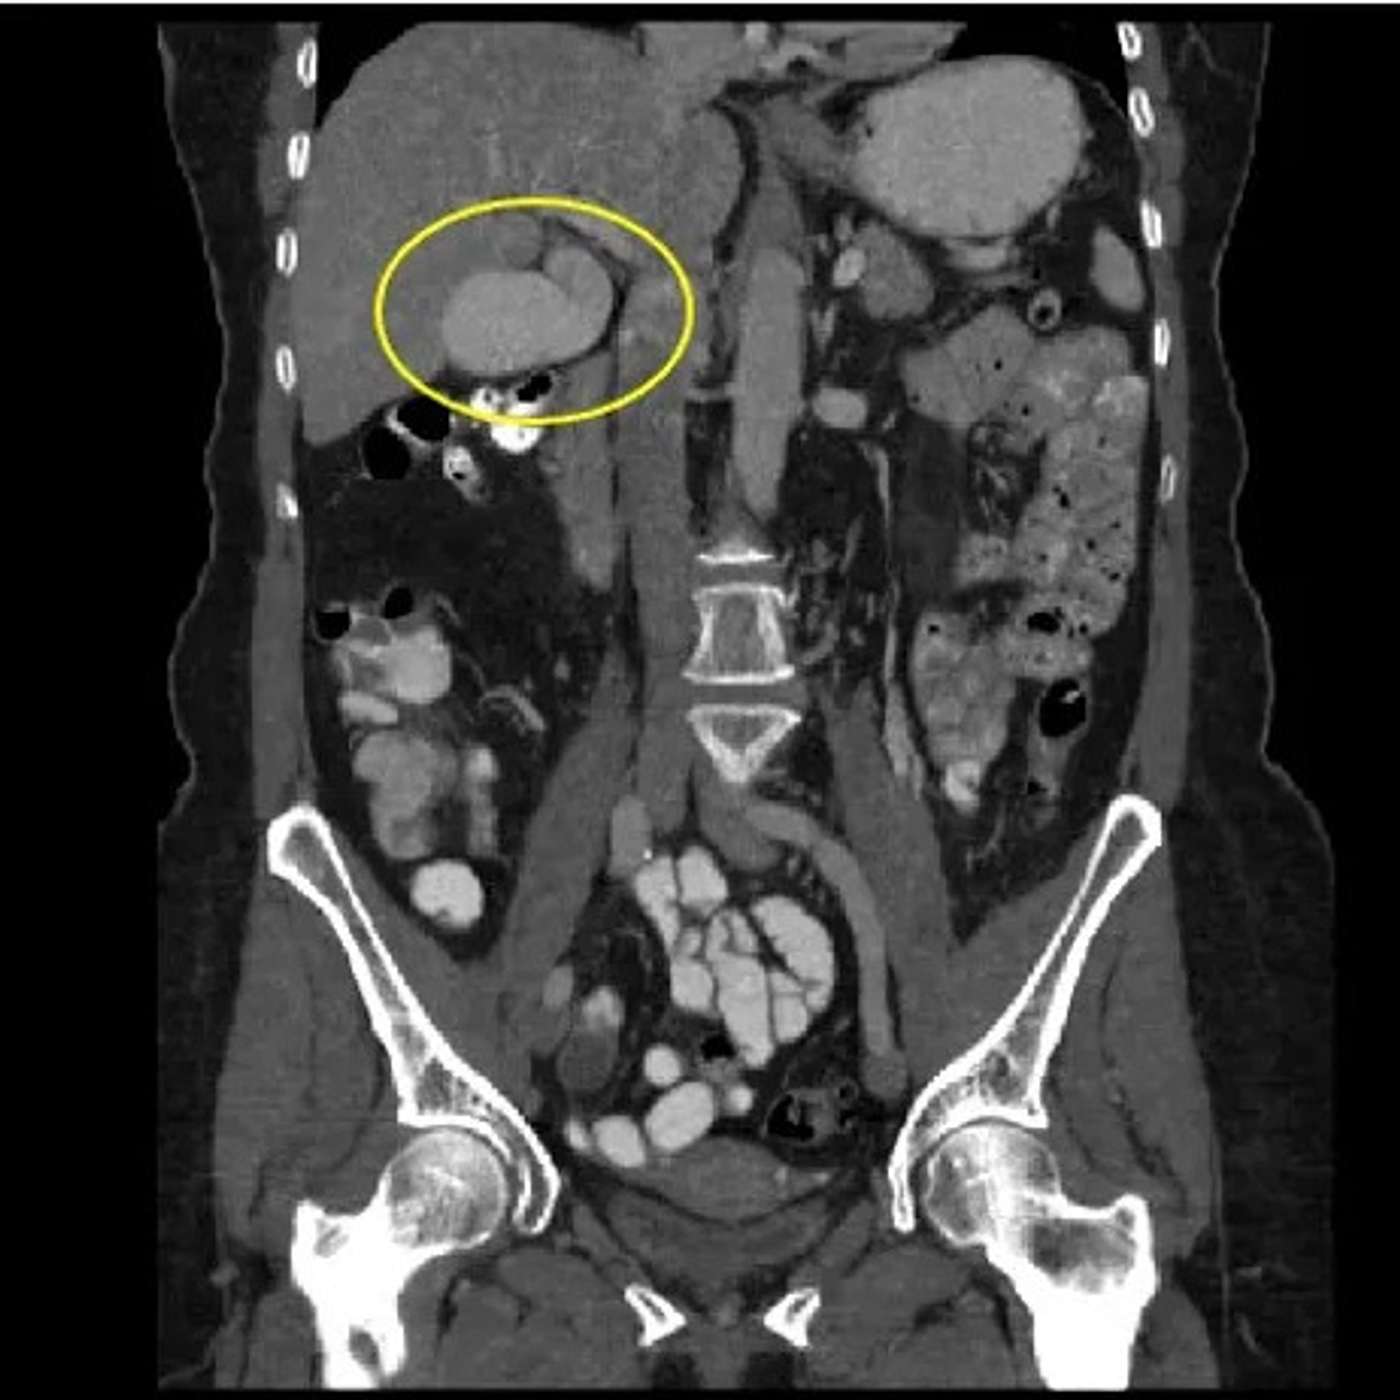

A phrygian cap gallbladder is a congenital anomaly of the gallbladder with an incidence of 4%. It can simulate a mass in the liver during hepatobiliary imaging and is sometimes mistaken for pathology. A Phrygian cap, however, has no pathological significance and normally causes no symptoms.